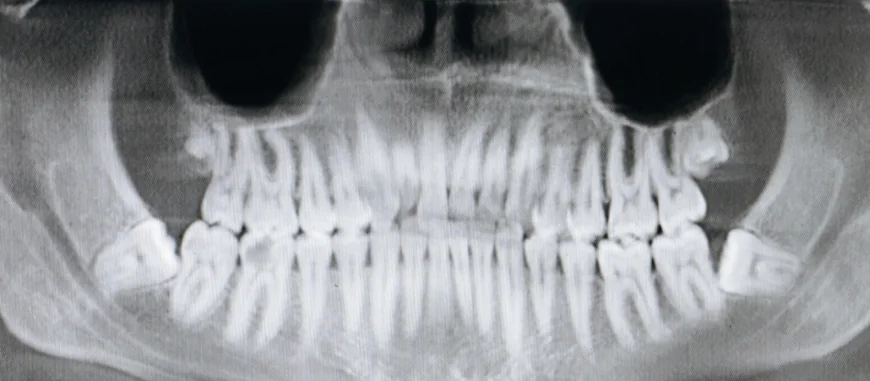

Dental health is an essential aspect of overall well-being, and modern technology has made it easier than ever to detect and prevent issues before they escalate. One of the most effective diagnostic tools available today is the panoramic dental X-ray. Unlike traditional X-rays that focus on small sections of your mouth, a panoramic X-ray captures the entire oral structure in a single image. For those wondering about the Panoramic Dental X-Ray Cost in Dubai, it’s important to understand that prices may vary based on the clinic, equipment used, and the level of expertise offered. Understanding the factors that influence the pricing can help you make informed decisions for your oral care.

A panoramic dental X-ray offers a broad view of the teeth, jaws, and surrounding structures. This imaging technique is particularly useful for identifying impacted teeth, jaw disorders, bone irregularities, and early signs of dental diseases. The detailed overview allows dental professionals to design more precise treatment plans. Because it covers a wide area in one shot, patients experience less radiation exposure compared to multiple traditional X-rays. This combination of efficiency, safety, and diagnostic power contributes to its perceived value.